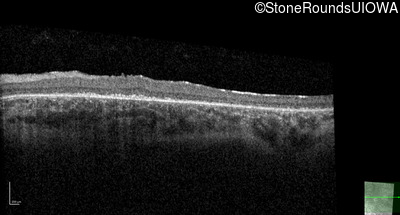

Optical Coherence Tomography - Right - 20/100 -1 sc

Exemplar / OCT Stack

Optical Coherence Tomography - Left - 20/100 -2 sc